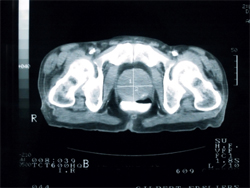

Prostatacancer

Många män får prostatacancer nu förtiden, och jag vill samla in pengar till forskningen så detta kan botas till 100%